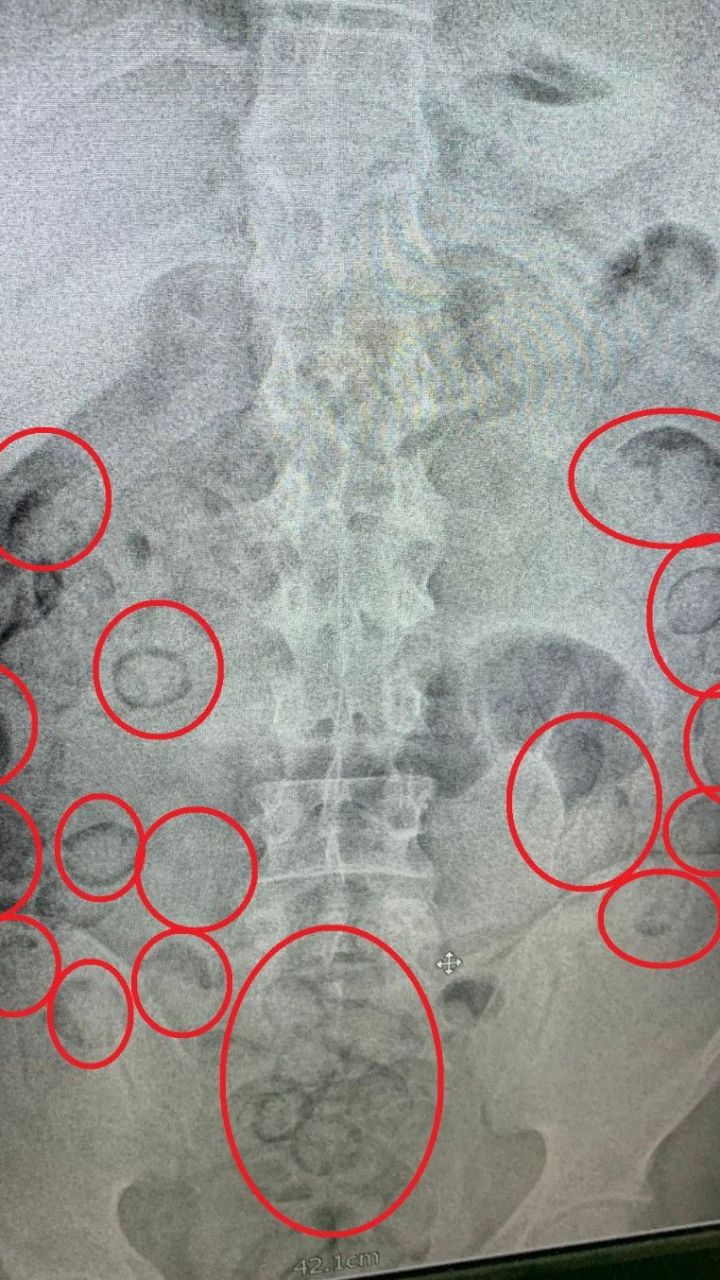

Şüpheliyi adım adım takip eden ekipler, E-90 Karayolu üzerinde otobüsten indiği anda operasyon başlattı. Gözaltına alınan A.M.’nin midesinde uyuşturucu taşıdığından şüphelenen polis, şahsı Aksaray Eğitim ve Araştırma Hastanesi’ne götürdü. Burada çekilen tomografi sonucunda midesinde yabancı cisimler olduğu tespit edildi.

101 Paket Uyuşturucu Midesinden Çıktı

Doktor kontrolünde ilaç içirilen şahsın midesinden, büyük tuvaletini yaptığı sırada 101 adet prezervatife sarılmış paket çıktı. Paketlerin içinde toplamda 433 gram metamfetamin maddesi ele geçirildi. Emniyetteki işlemleri tamamlanan uyuşturucu taciri, çıkarıldığı mahkemece tutuklanarak cezaevine gönderildi.